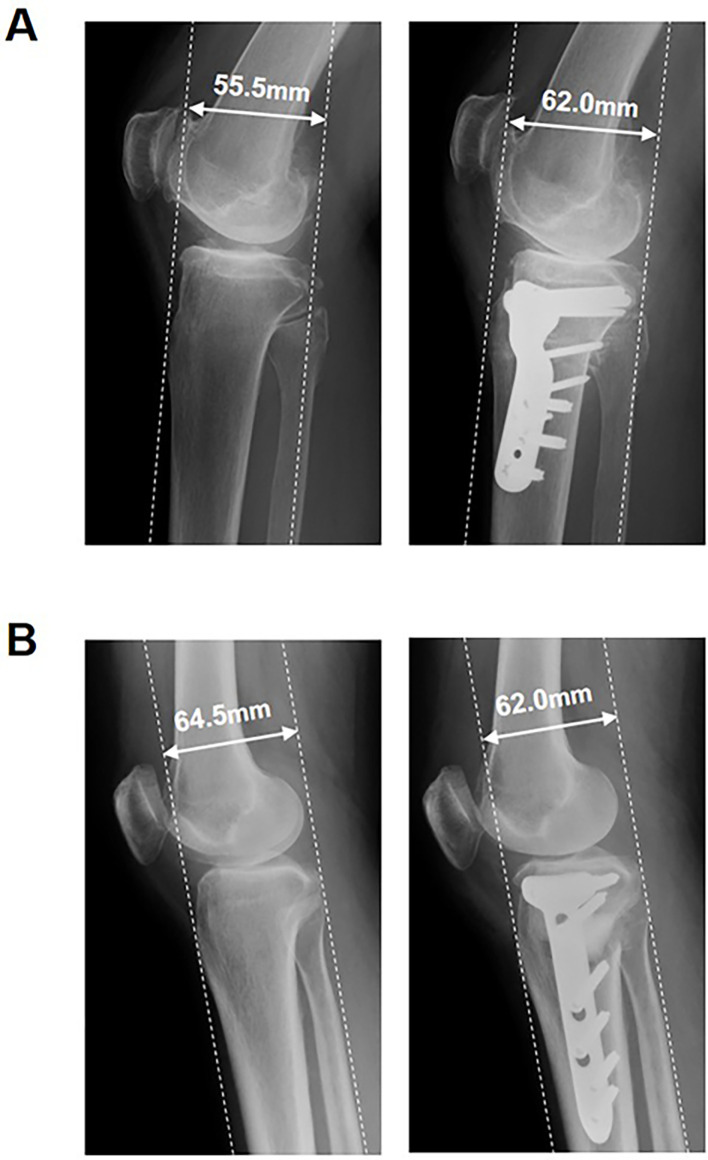

Methods: One hundred consecutive knees with osteoarthritis that underwent OWHTO (50 knees) or CWHTO (50 knees) were investigated retrospectively. The femorotibial angle (FTA) was measured on AP radiographs of the knee. AP displacement of the TT, posterior tibial slope (PTS), the modified Blackburne-Peel index (mBPI), and the modified Caton-Deschamps index (mCDI) were measured on lateral radiographs of the knee.

Results: Patients had a mean correction angle of 12.58 ± 2.84° and 18.98 ± 5.14° (P < 0.001), with a mean AP displacement of TT of 0.84 ± 2.66 mm and 7.78 ± 3.41 mm (P < 0.001) in OWHTO and CWHTO, respectively. The AP displacement of the TT per correction of 1° was significantly greater in CWHTO than in OWHTO (P < 0.001). A significant correlation was found between the correction angle and AP displacement of the TT in CWHTO (r = -0.523, P < 0.001), but not in OWHTO. The change of PTS per correction of 1° was significantly greater in OWHTO than in CWHTO (P < 0.001). The changes of mBPI and mCDI per correction of 1° were significantly greater in CWHTO than in OWHTO (P < 0.001 and P < 0.001, respectively).